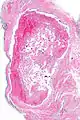

Intravascular papillary endothelial hyperplasia is a rare, benign tumor. It may mimic an angiosarcoma, with lesions that are red or purplish 5-mm to 5-cm papules and deep nodules on the head, neck, or upper extremities.[1][2]: 592